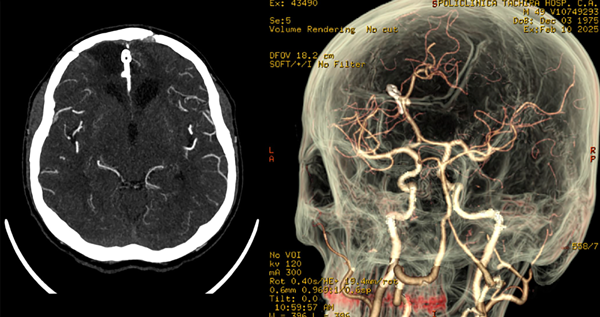

Posteriormente es trasladado a terapia intensiva intubado donde se mantiene bajo sedoanalgesia en infusión por 24 horas y, tras reversión, se evidencia Glasgow 11/15 (respuesta verbal: 4, respuesta motora: 6), sin déficit neurológico aparente. Se retira drenaje subcutáneo a las 48 horas postoperatorias. Se indica tomografía cerebral simple (Figura 3) con buen control de evacuación de las colecciones hemáticas, y la AngioTC con correcta exclusión del aneurisma (Figura 4). El paciente tiene una óptima evolución.

Figura 4. Angiotomografía cerebral. En corte contrastado axial se observa: cuerpo hiperdenso en fisura interhemisférica que genera discreto efecto Hounsfield correspondiente con clip simple de palas rectas normoposicionado, área de encefalomalacia orbitofrontal de predominio izquierdo. En reconstrucción 3D: exclusión de la circulación de aneurisma de ACAa, clip normoposicionado, preservación de ramos vasculares distales.